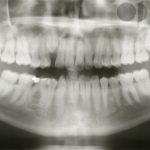

– Expansión del maxilar (paladar). Cuando el paladar es estrecho (por ejemplo en casos de respiración oral en los que la lengua permanece baja y no contribuye al desarrollo transversal normal del techo de la boca) se puede producir una mordida cruzada (las muelas de arriba muerden por dentro de las de abajo).

Ejemplo de mordida cruzada lateral. La parte superior debería de cubrir por fuera a la inferior.